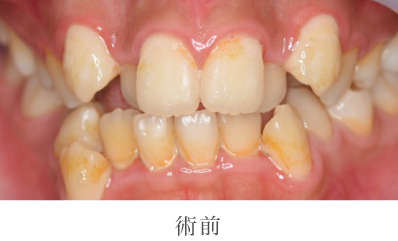

02

クリーニング・

歯科検診の詳細

- 主訴

- 口臭が気になる

- 治療期間

- 1日

- 治療内容

- 染め出し、歯石除去、ポリッシング(艶出し)

- 治療のリスク

- 術後しみる可能性があります

- 治療費

- 保険診療に準ずる

院長のコメント

全体的に歯石や汚れ(プラーク)が付着し歯肉に炎症が見受けられました。歯周病や口臭の原因である汚れを除去し磨き上げました。歯並びの影響もあり、どうしてもご自身で磨きにくい場所もありますがその際は専門である私たちに是非ご相談下さい。